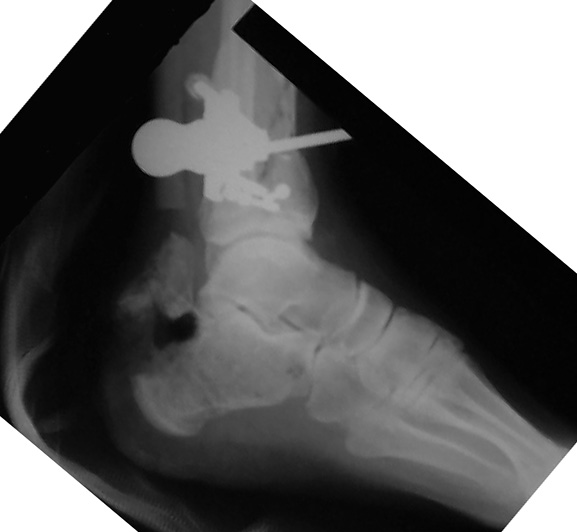

Tibia Fx ForumCase 1

I would appreciate treatment suggestions.My patient is a 30 year old with a very comminuted tibia fracture 6 weeks ago.It was grade 3B open. Initial treatment included irrigation, debridementClick images to enlarge.

and a hybrid external fixator including femur, tibia and foot. Screwswere placed in the plateau and plafond and a free flap plus STSG. Theskin is ok but atrophic. The femoral pins were removed and knee motionstarted at 6 weeks. There is no sign of callus. There is one pin inthe one large fragment of the diaphysis. All the pieces are lined upreasonably well. The XF pins are ok. Suggestions? Thank you.